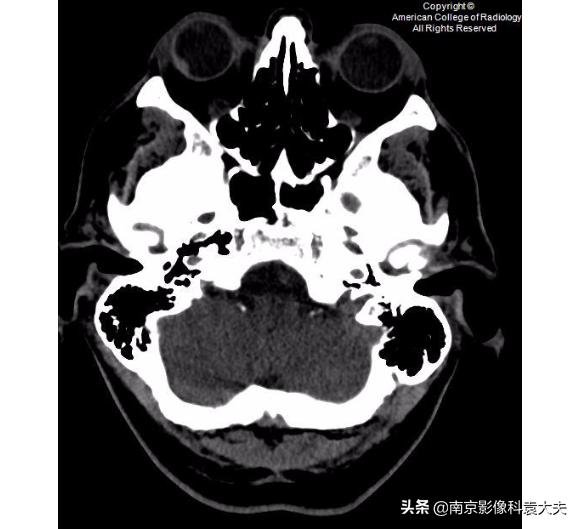

非对比增强CT(平扫)更低一层面显示沿右眼球外侧壁的高密度的眼内出血(箭头)。眼内出血可能是眼外伤的一

右眼矢状位非对比增强CT(平扫)显示前房(箭头)塌陷。这可以在角膜裂伤的情况下看到。